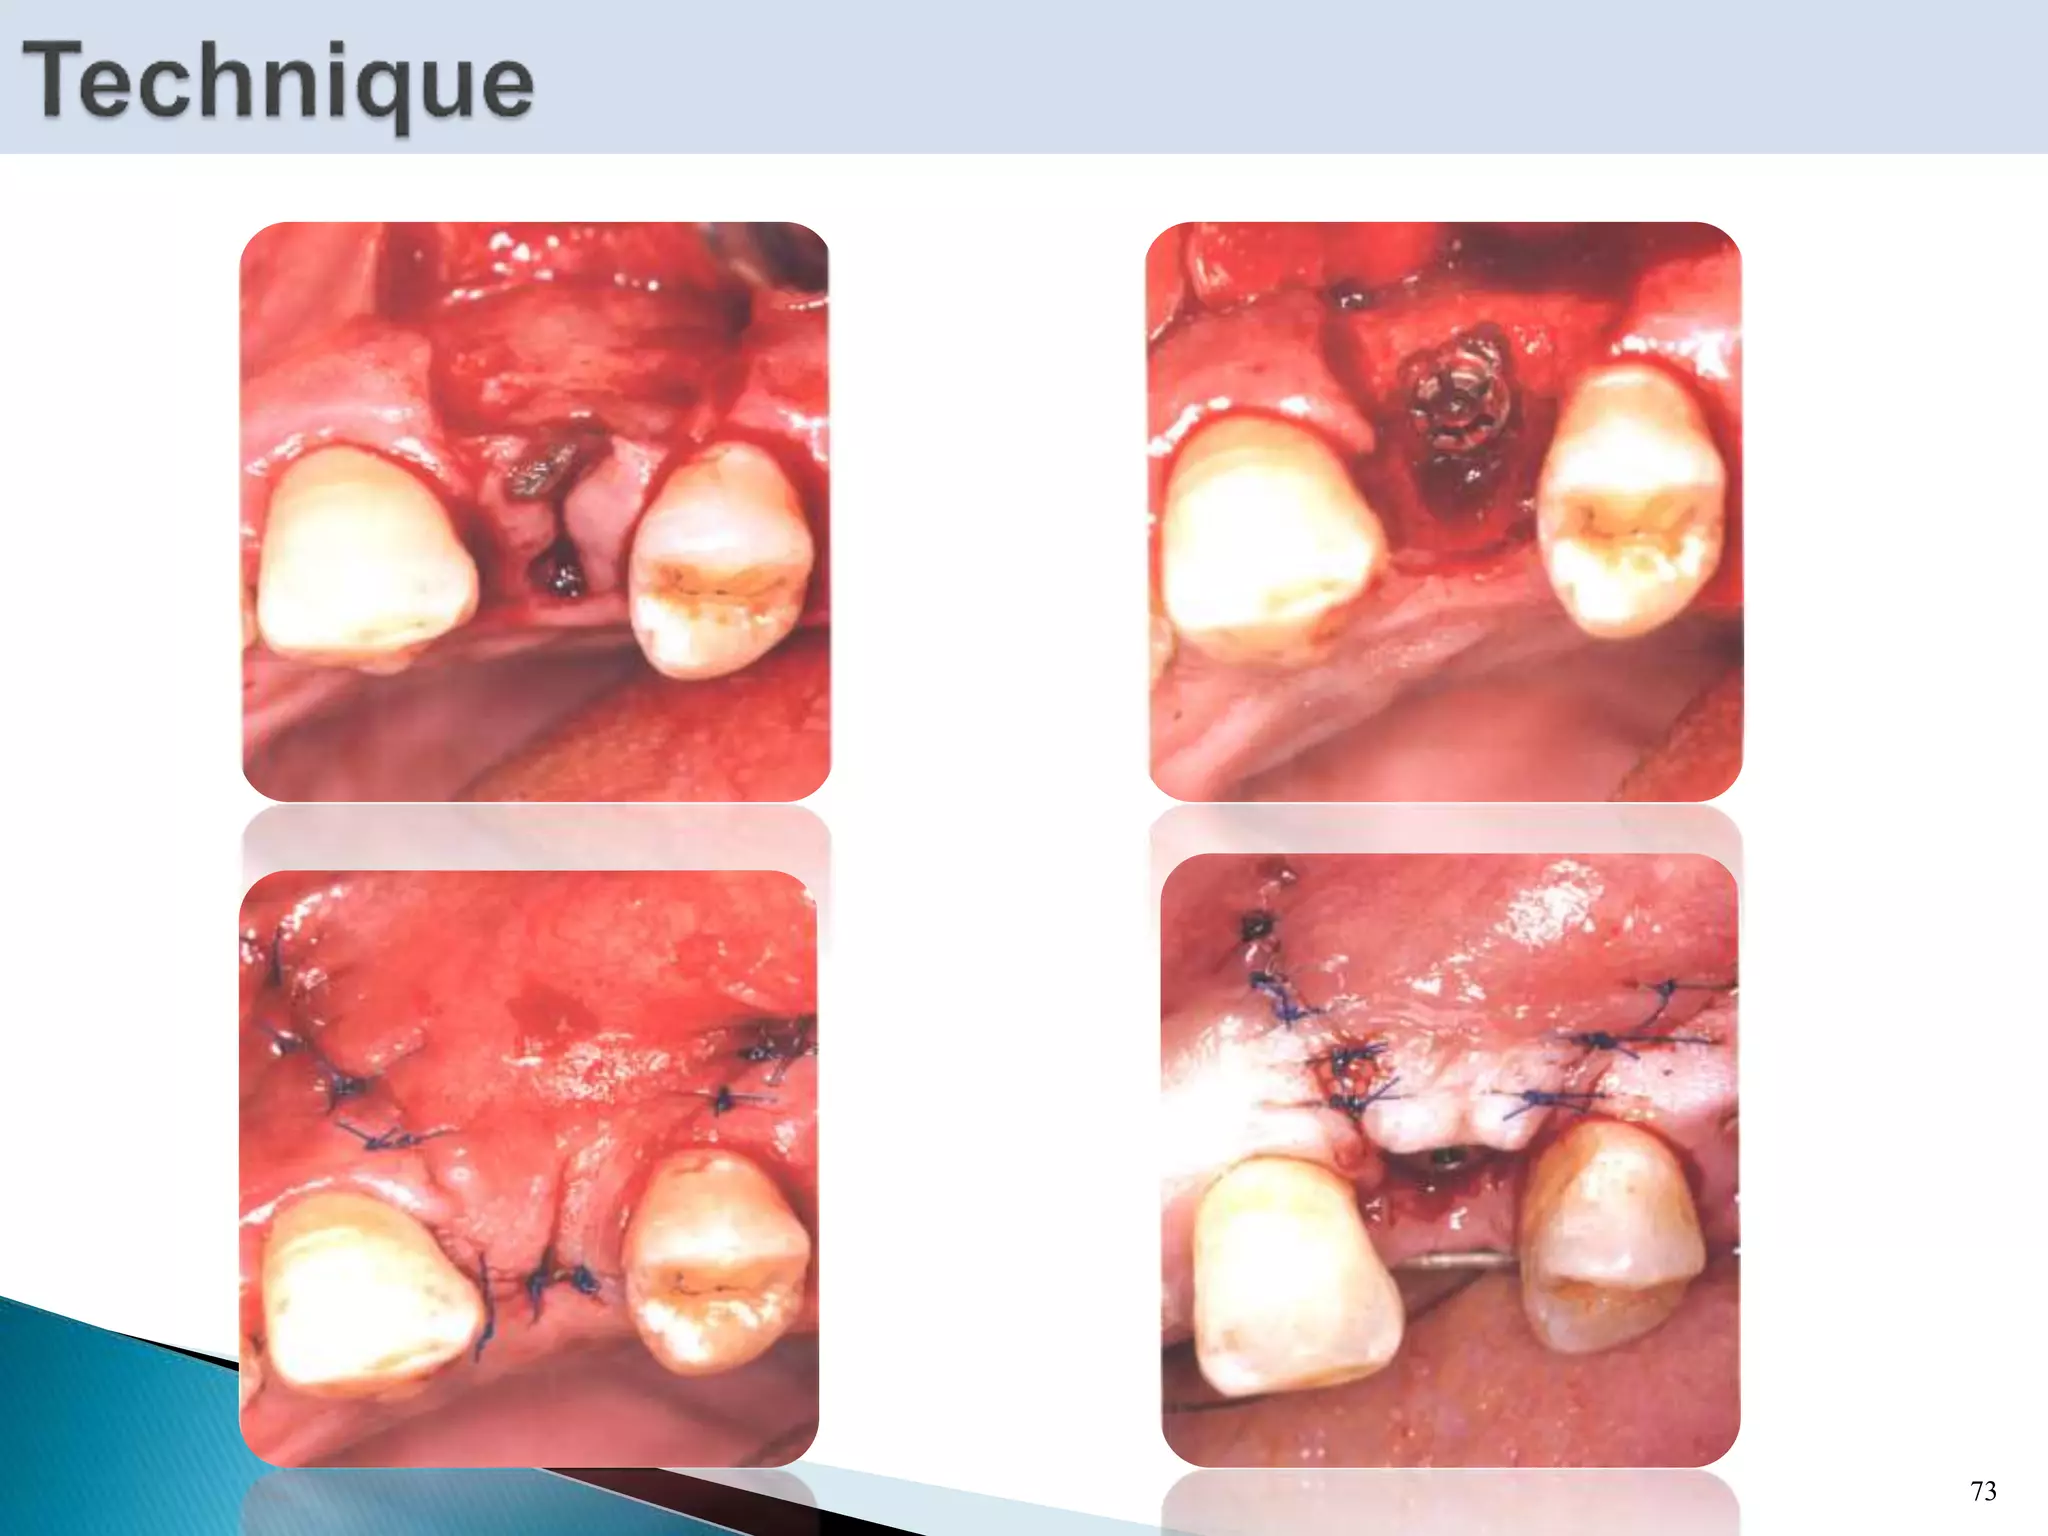

70

 Most common method among clinicians for primary soft

tissue closure in the oral cavity.

72

73